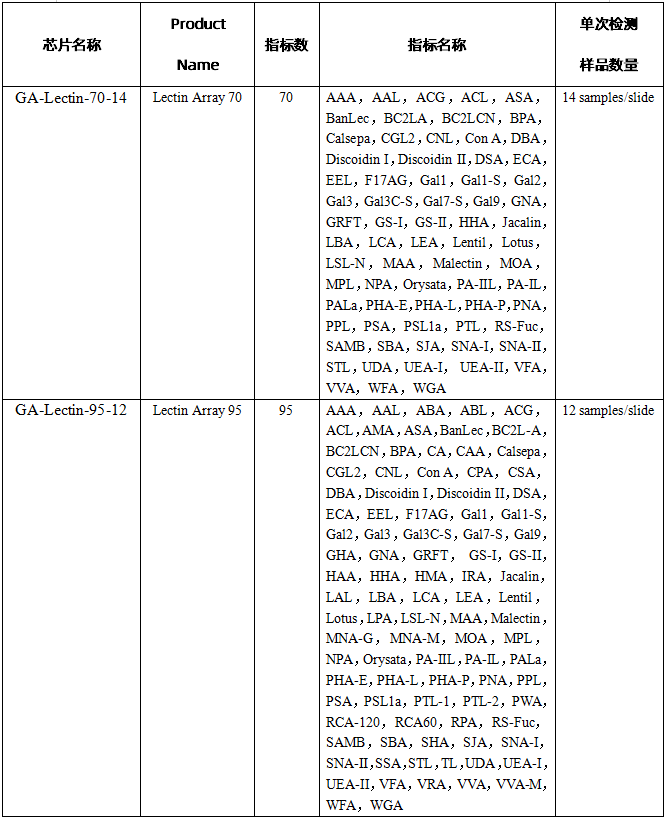

| 凝集素芯片应用方向

| 凝集素芯片产品列表